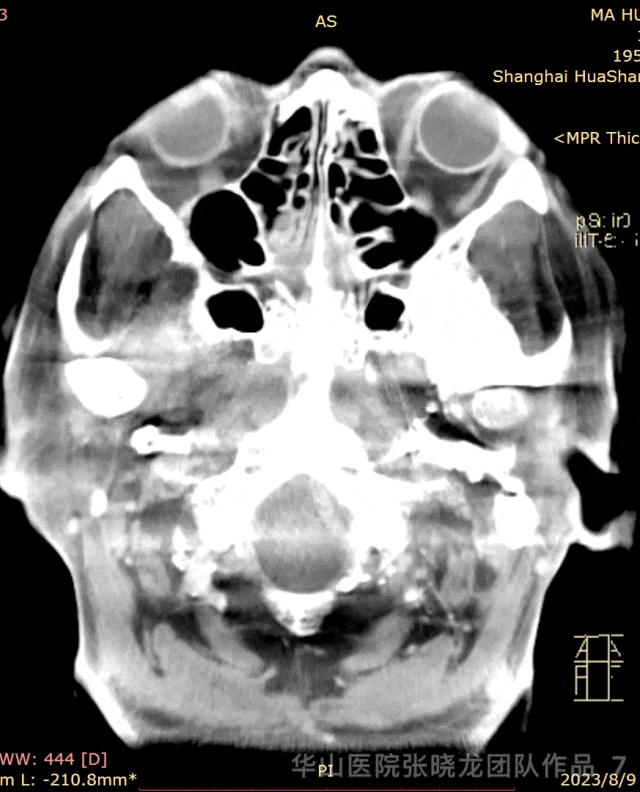

图 7 GIF. 术后复查Dyna-CT未见出血。